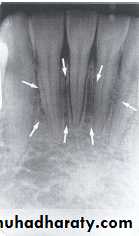

BONY LANDMARKS OF THE MANDIBLE

Radiographs of the region of the mandibular symphysis in infants demonstrate a radiolucent line through the midline of the jaw between the images of the forming deciduous central incisors. This suture usually fuses by the end of the first year of life, after which it is no longer radiographically apparent.GENIAL TUBERCLES

:

The genial tubercle are tiny bumps of bone that serve as the attachment sites for the genioglossus and geniohyoid muscles, its located on lingual aspect of the mandible. On mandible periapical radiograph the genial tubercle appears as a ring shaped radiopacity below the apices of the mandibular incisor.

LINGUAL FORAMEN

The lingual foramen is a tiny opening or hole in the bone located on the internal surface of mandible, its located near the midline and surrounded by genial tubercle. Radiographically, the lingual foramen appears as small radiolucent dot located inferior to the apices of mandibular incisor.